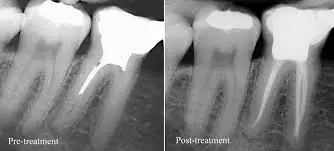

The decision to extract wisdom teeth is based on clinical examination and imaging findings. OPG (panoramic) X-rays provide an overview of all four wisdom teeth and their relationship to surrounding structures. When greater detail is needed, particularly for lower wisdom teeth near the inferior alveolar nerve, CBCT (cone beam computed tomography) provides three-dimensional views that allow precise assessment of nerve proximity, root morphology, and bone density. This imaging-guided approach significantly reduces surgical risks and enables your oral surgeon to plan the optimal extraction technique for your specific anatomy.

The extraction procedure itself varies in complexity depending on whether the tooth is erupted, partially erupted, or fully impacted within bone. Simple extractions of erupted wisdom teeth involve loosening the tooth with an elevator instrument and removing it with forceps under local anesthesia. Surgical extractions of impacted teeth require making a small incision in the gum, sometimes removing a small amount of bone, and often sectioning the tooth into pieces for easier removal. Both approaches are performed under effective local anesthesia, and sedation options are available for patients who are anxious or have particularly complex cases.